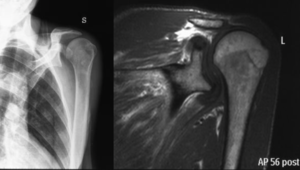

Standard shoulder radiographs, including anteroposterior, axillary lateral and scapular Y (outlet) views, may demonstrate decreased acromiohumeral distance, glenohumeral arthritis, subacromial spurs, acetabularization of the acromion, femoralization of the humeral head, and implant or anchor migration.[98][99]

It can also be used to rule out chondrolysis, anchor migration or prominence, and acromial fracture. Among evaluation techniques, the most widely accepted reference standard is magnetic resonance imaging which allows visualization of the tendons and does not involve radiation exposure. Intra-articular contrast may be used in association with magnetic resonance imaging to increase the sensitivity for detecting a recurrent tear.[100]